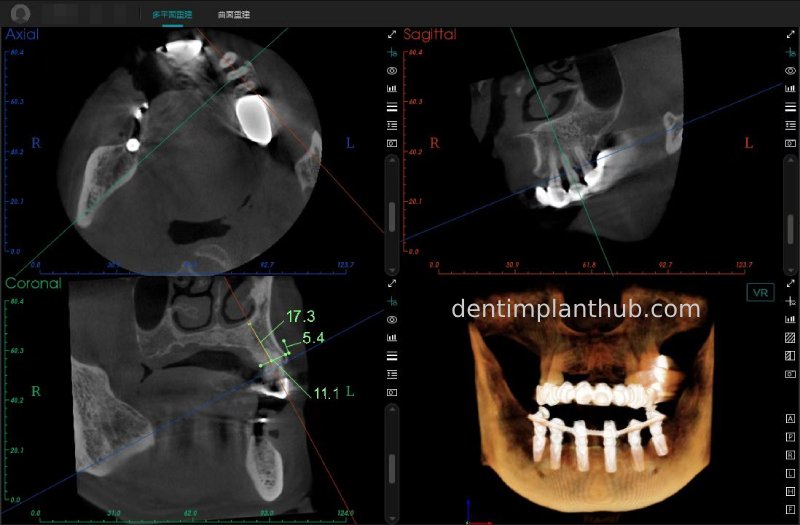

CBCT review results on 13 May '24

46

44

42

32

34

36